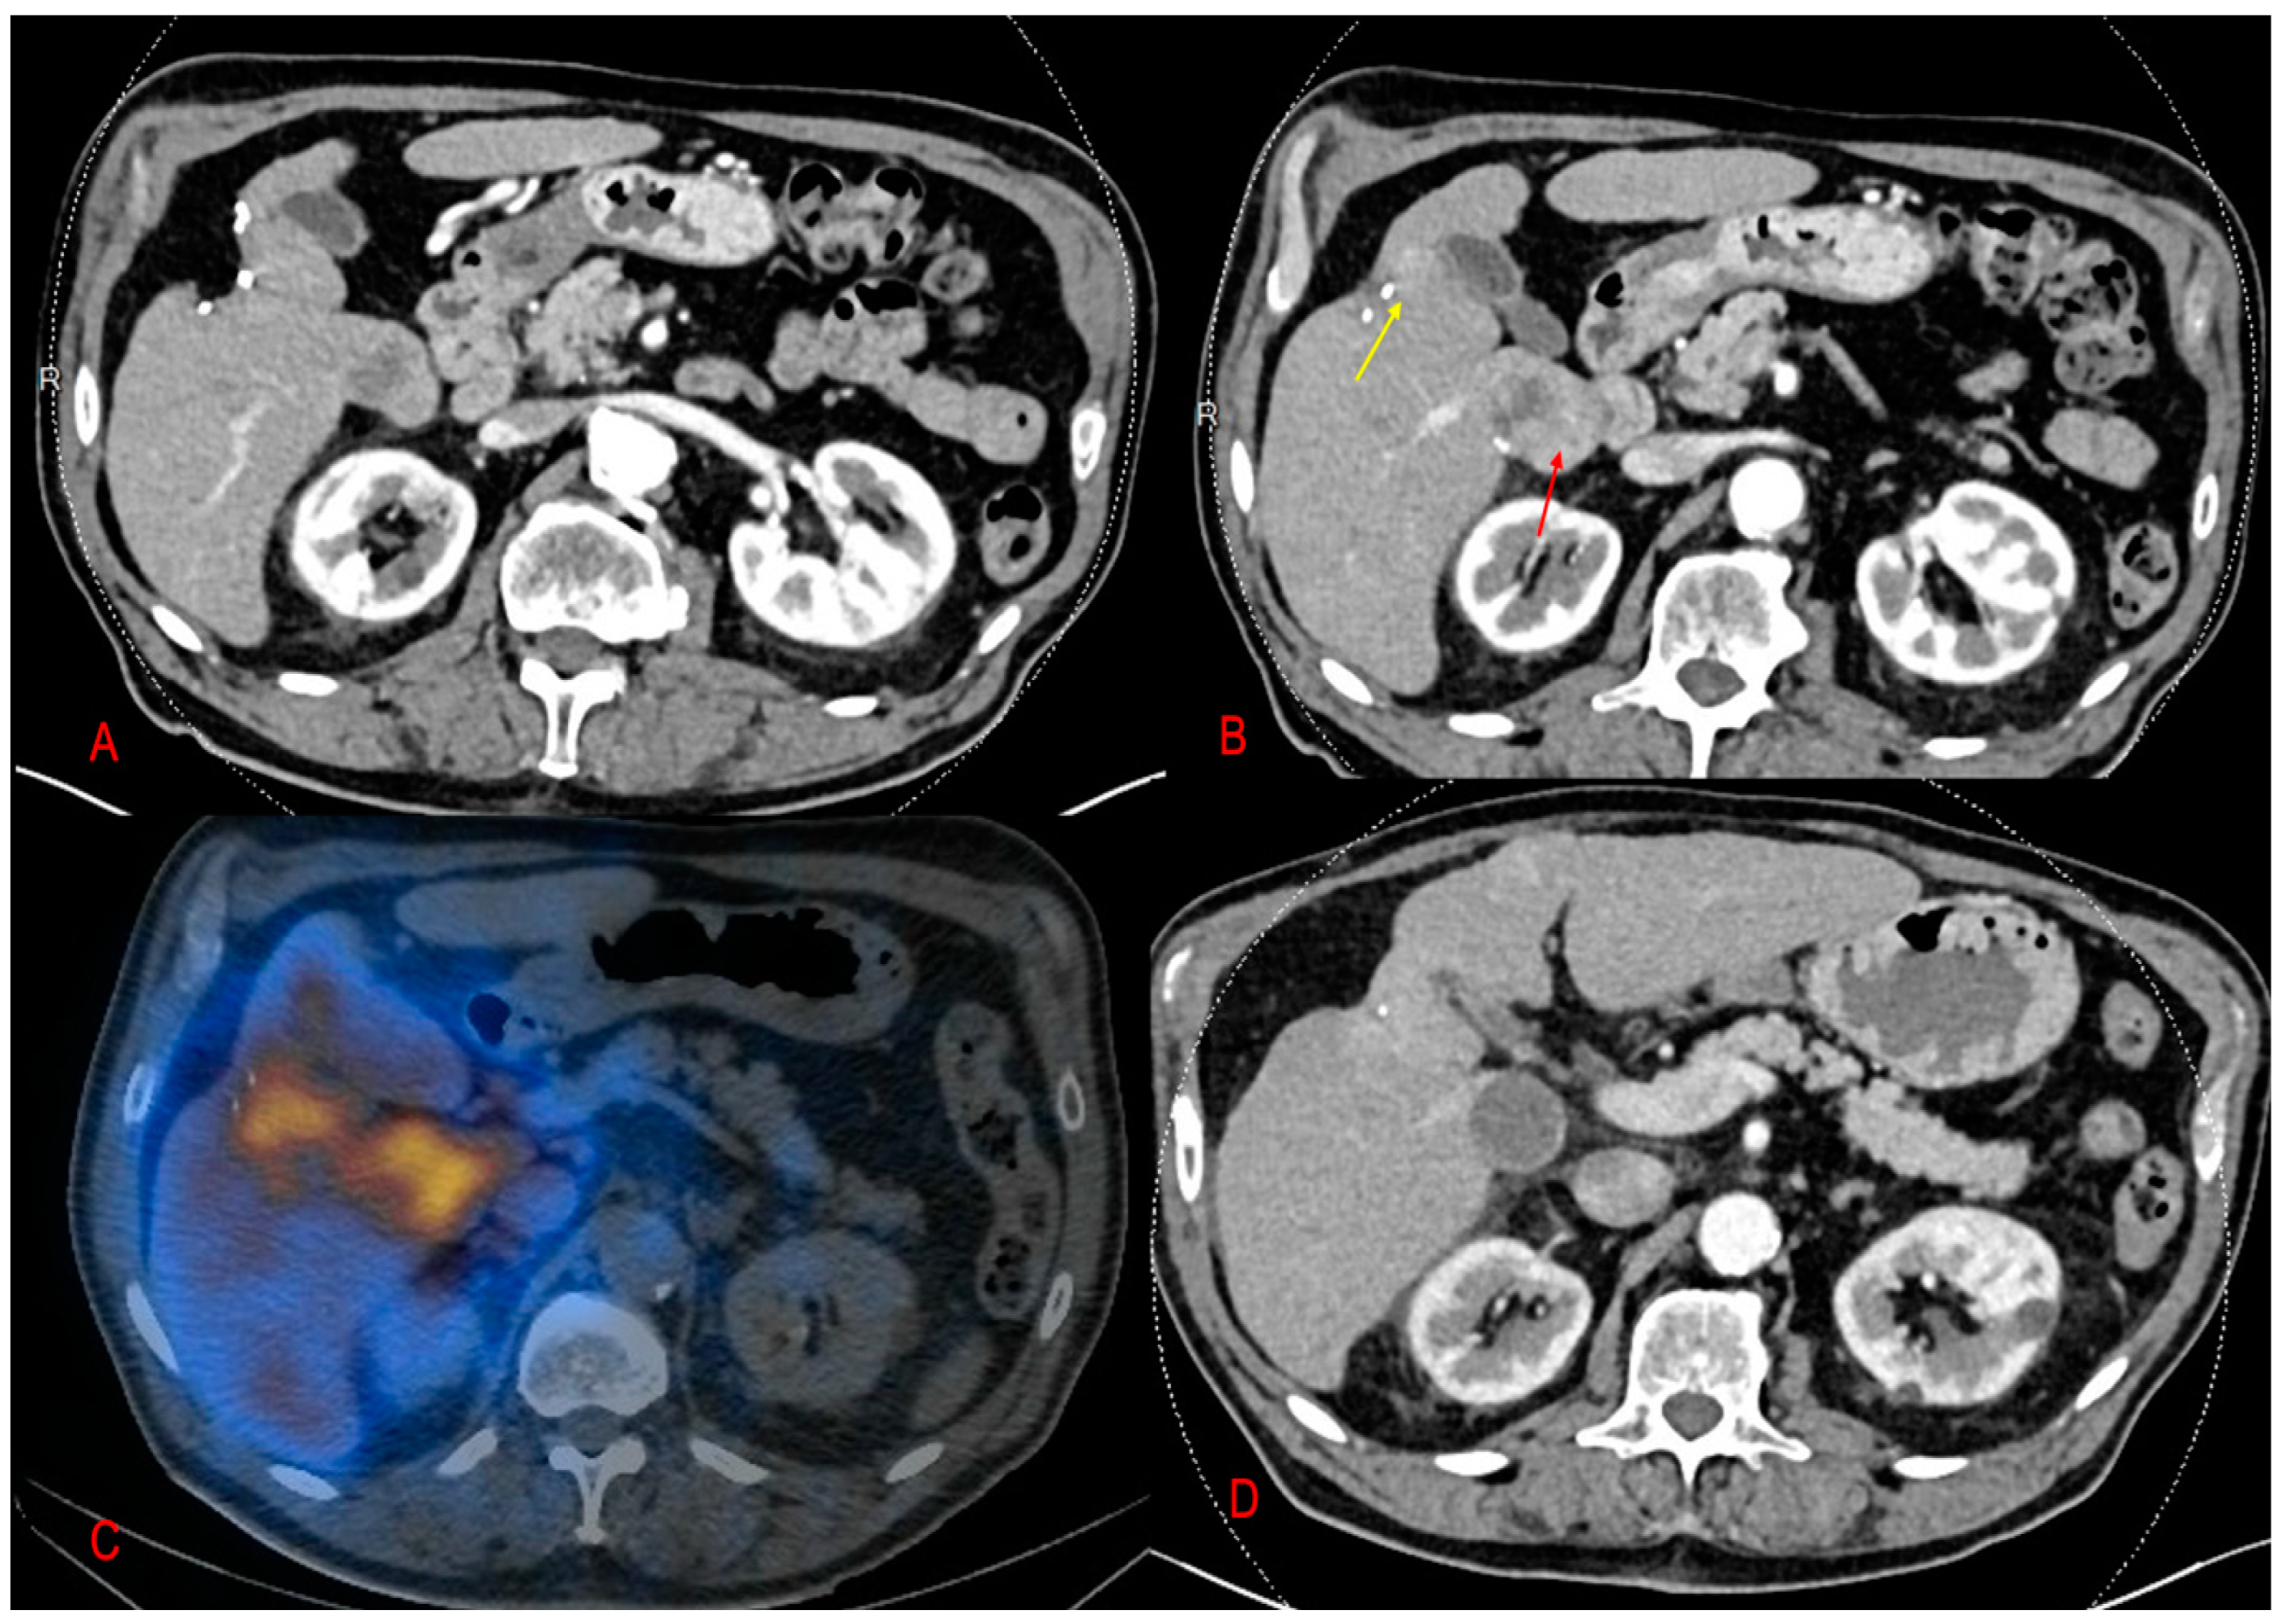

2. Results

2.2. MAA-Based Dosimetry Analysis

2.3. 90Y-Based Dosimetry Analysis